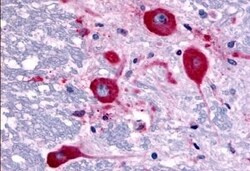

TAOK1 Polyclonal Antibody for IHC (P)

| Immunohistochemistry (Paraffin) | |

| Synthetic 16 amino acid peptide from internal region of human TAOK1. | |